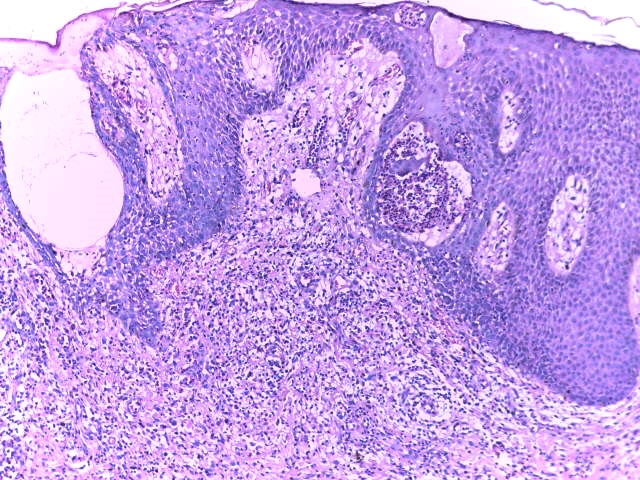

El pénfigo vegetante, es una variante rara del pénfigo vulgar (PV) corresponde a 1-2 % de los casos, las características clínicas e histopatológicas habitualmente permiten la diferenciación en 2 subtipos descritos: Neumann y Hallopeau, pero en ocasiones pueden presentarse de forma simultánea o secuencial. Las lesiones adoptan un aspecto vegetante afectando cualquier área de la piel, pero predomina en áreas intertriginosas y mucosa oral. Presentamos el caso de una paciente de 31 años de edad, con 1 año de evolución de placas eritematosas con vesículas y pústulas en la superficie cutánea, simulando dermatosis eccematosas que no permitían realizar el diagnóstico. Luego de la suspensión del tratamiento con esteroides sistémicos que recibía, se logró establecer el diagnóstico definitivo al evidenciar las características clínicas del pénfigo vegetante y corroborar con el estudio histológico e inmunofluorescencia directa.

Pemphigus vegetans, is a rare variant of pemphigus vulgaris (PV) corresponding to 1-2% of cases, clinical and histopathological characteristics usually allow the differentiation into 2 described subtypes: Neumann and Hallopeau, but sometimes they can present simultaneously or sequentially. Lesions adopt a vegetative appearance, affecting any area of the skin, but predominate in intertriginous areas and oral mucosa. We present the case of a 31-year-old female, who presented clinical manifestations of both variants, making their differentiation impossible, simulating eccematous dermatosis. After suspension of systemic steroids, final diagnosis was made based on clinical, histologic and direct immunofluorescence studies.